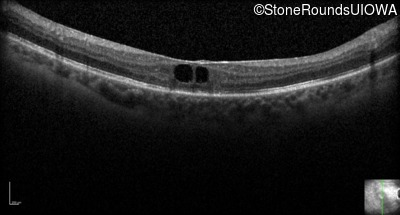

Optical Coherence Tomography - Right - 20/50 +2

Exemplar / OCT Stack